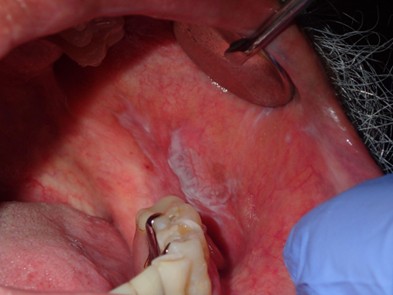

Figure 3. Bimanual Palpation of the Floor of Mouth

Intraoral and extraoral bimanual palpation technique used to assess the floor of mouth. This approach allows for detection of induration, masses, or submucosal changes not apparent on visual examination alone.